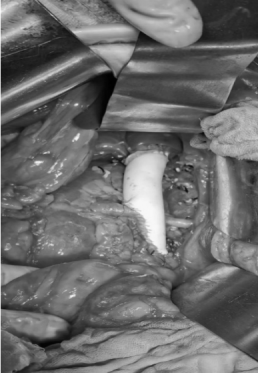

第二次人工血管置换

将情况与患者及家属充分沟通后,患者手术意愿强烈。邰升教授团队联合王海平教授团队制定详细的术前手术规划,拟行腹膜后肿物联合右肾及肾上腺切除、右侧腹膜后廓清、下腔静脉二次人工血管重建术。一周前,在麻醉科、输血科、手术室的大力配合下,邰升教授团队联合王海平教授团队再次为患者进行了手术治疗。术中,见原手术切口下方广泛粘连、十二指肠横结肠致密粘连于原术区,肿瘤侵犯周围组织致密广泛且包绕压迫原置换的人工血管,人工血管周围炎性粘连严重,这一切均使显露、切除肿物变得极其困难。